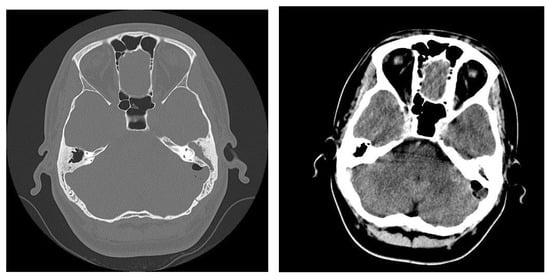

3.1.2. Computed Tomography and Magnetic Resonance Imaging

| MRI Aspects | Number of Patients | Percentage |

|---|---|---|

| Edema | 128 | 100% |

| Cholesteatoma | 40 | 31.25% |

| Exocranial extensions | 40 | 31.25% |

| Intracranial extensions | 32 | 25% |

| Inner ear damage | 20 | 15.62% |